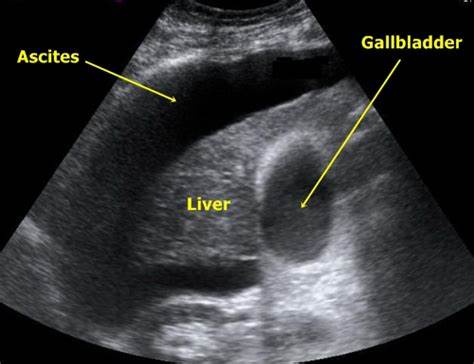

肝硬化腹水

肝硬化腹水的B超影像表现